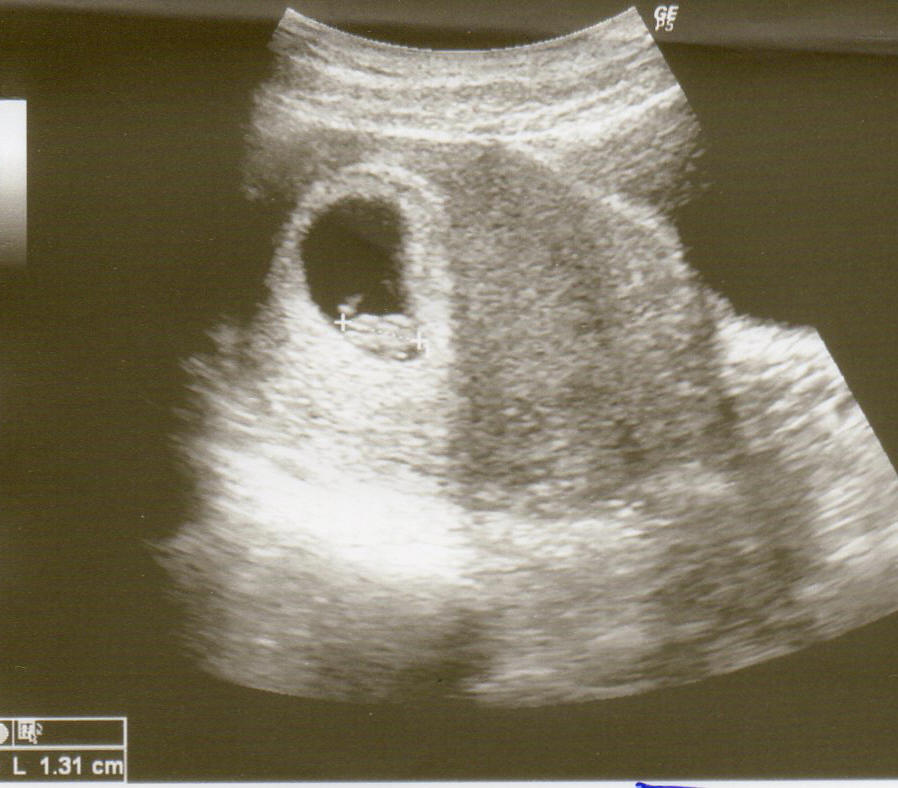

so jetzt versuche ich mal das Bildchen hochzuladen...

Ich bin jetzt bei 7+5. (wobei sich da Ärzte da um 2 Tage unterscheiden).

Baby ist nach wie vor ne Woche zurück aber nicht mehr 9tage und viel wichtiger das Herz schlägt. Er war sehr nett und konnte mich verstehen. Aber ich soll mich entspannen und gesund leben.